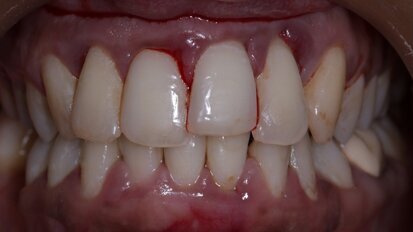

Bringing anterior direct composite restorations to life with histologic layering protocols

Composite resin is a material that is able to mimic natural tooth structure, its optical properties and aesthetics. Often due to trauma or caries, the ...